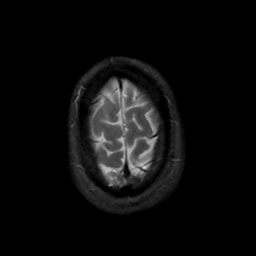

MR Study #4, March 3, 1991 -- Slice #45

[Home][Help][Clinical][Tour 1][Tour 2] Slice 45